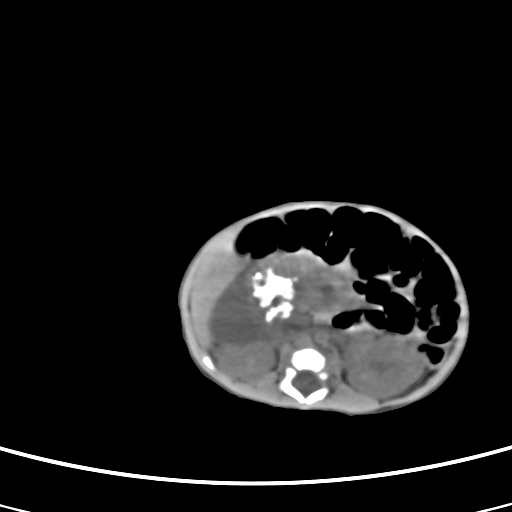

患儿,男性,出生后2天,在胎儿时b超已发现病变,患儿一般情况可。因病变部位偏向于右侧肾上腺区,目前考虑为神经母细胞瘤,不知各位能否支持。

病灶内未见明显脂肪密度。

反对定位在右肾上腺区的说法,那么神经母细胞瘤也可以暂时不予考虑。请看下图:

下面这幅图中,似乎可以见到肿瘤的薄包膜,其后与右肾之间的又是什么东西呢?这关系到肿瘤的定位、定性。我考虑病灶是位于肝十二指肠韧带内的畸胎瘤可能性比较大。请各位老师仔细看一下:

病灶巨大,位于右侧肾上腺区,与周围组织分界欠清,内见不规则钙化影,无明显脂肪组织,首先考虑神经母细胞瘤,但畸胎瘤不能排除。

手术结果为畸胎瘤